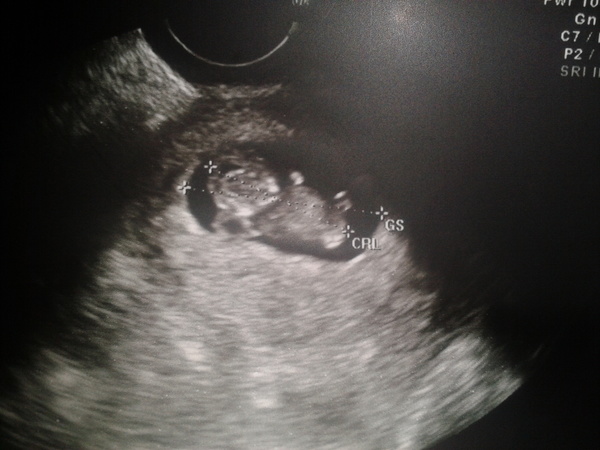

я тоже на первом узи прям офигела))) такие танцы)))

а потом уже меньше))) ибо в экран помещается что-то одно))) в основном я видела или попу или ногу)))